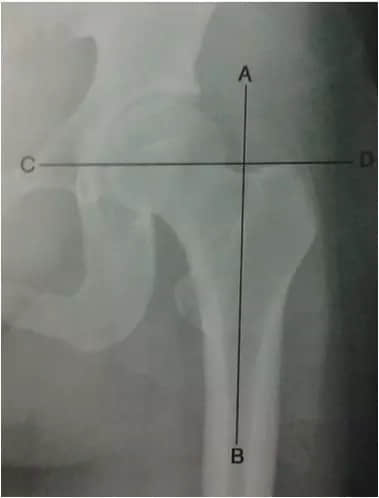

5 Skinner線

成人髖關(guān)節(jié)正位片上,從股骨大轉(zhuǎn)子頂端做股骨縱軸線的垂線,正常應(yīng)過(guò)圓韌帶窩或其下方,圓韌帶窩直上述兩線交點(diǎn)距離約為4-5厘米,若Skinner線超過(guò)圓韌帶窩,提示股骨頸或大轉(zhuǎn)子錯(cuò)位骨折。